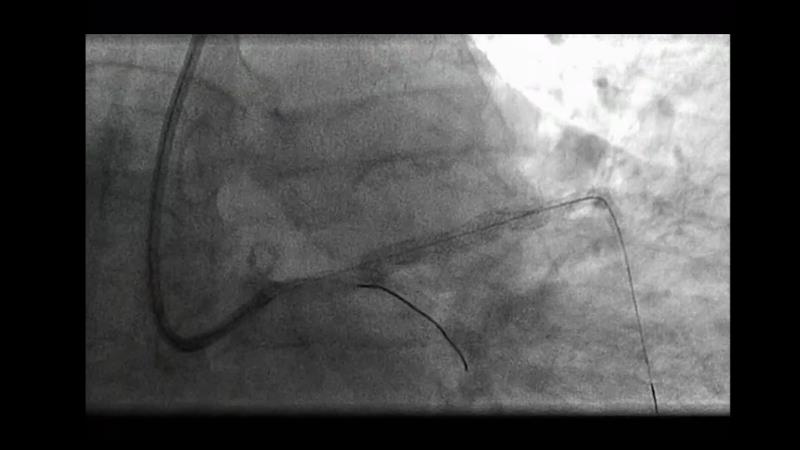

Follow the case study of this 70-year-old ex-smoker male patient with HTN, dyslipidemia, previous primary PCI to proximal and mid LAD because of anterolateral STEMI, presenting with syncope, and find out, through the debates around his treatment, how to use physiology in 2023.

- To learn how physiology pullbacks and angiography co-registration can help to define the patterns of atherosclerotic disease and guide treatment strategy

- To learn key tips and tricks to obtain accurate physiological measurements